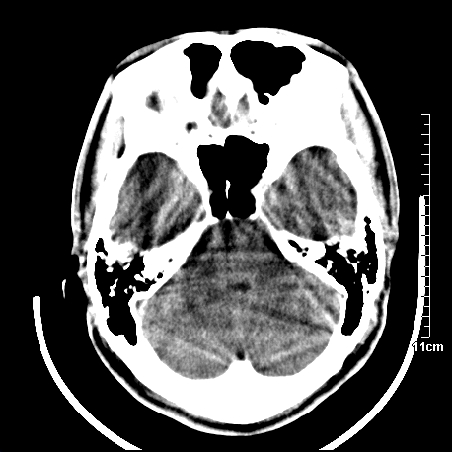

头晕.头痛间断意识恍惚1周 m/21y

4天上述症状加重伴左侧肢体发软,复查ct,

这么年青,不会是梗塞吧,可能是感染性病变

病人在家输液时出现发热.头痛.恶心等不适

右侧放射冠区混杂密度灶,边缘不清,病人较年轻,结合有发热病史,支持感染性病变,建议密切结合临床可抗感染治疗后复查。

右侧颞叶病变定性困难,既然发病急,又有发热,脑脓肿不能除外。

右侧颞叶混杂密度灶,强烈建议:增强ct检查